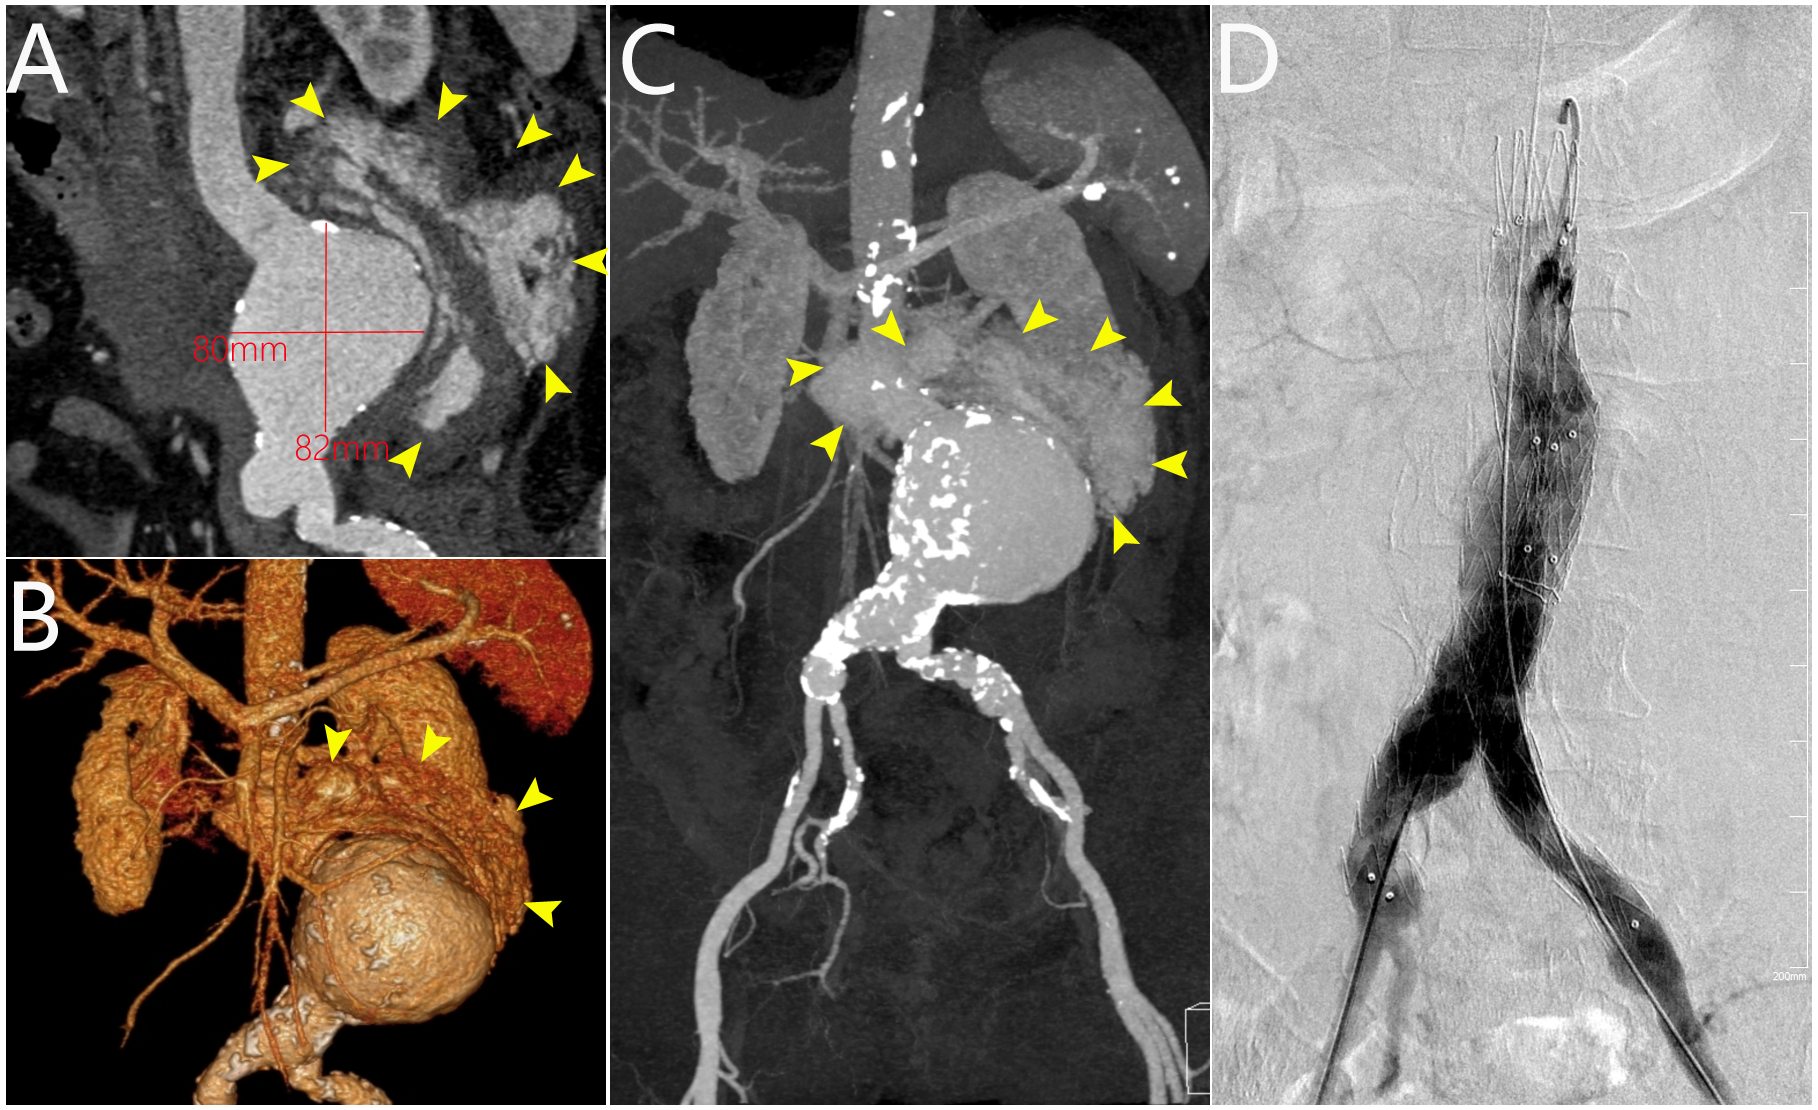

A 72-year-old woman presented with acute onset of abdominal pain accompanied by nausea and vomiting for 10 hours. Computed tomography angiography (CTA) revealed a ruptured abdominal aortic aneurysm (AAA) measuring 80 × 78 × 82 mm with extensive intraperitoneal hemorrhage (Figure A-C, arrows). Because of the emergent nature of her condition, the patient underwent emergency endovascular repair with Endurant 25-16-166 and 16-20-124 stent grafts (Medtronic) placed in the abdominal aorta and bilateral iliac arteries (Figure D, Video). The postoperative course was uneventful, and the patient was discharged to a rehabilitation center after 3 days.